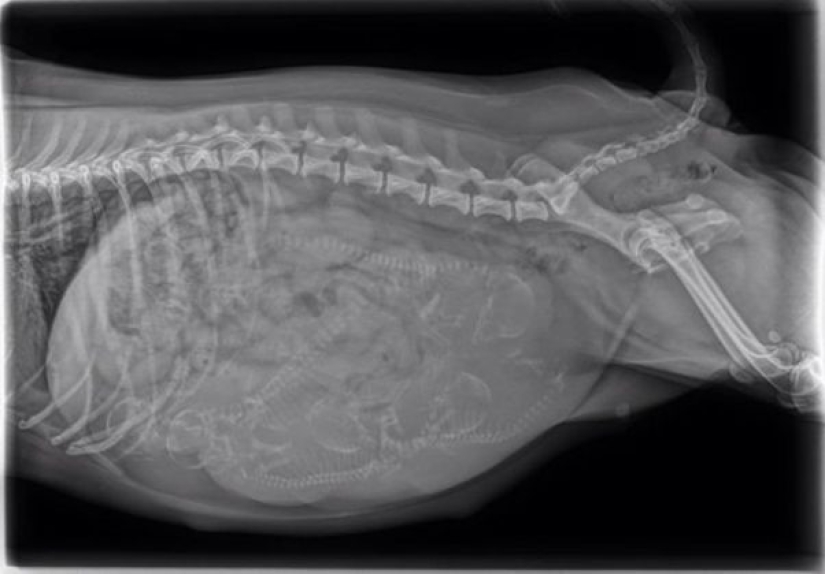

13. "Radiografía del vientre embarazado de mi perra: podemos contar 5 cachorros".